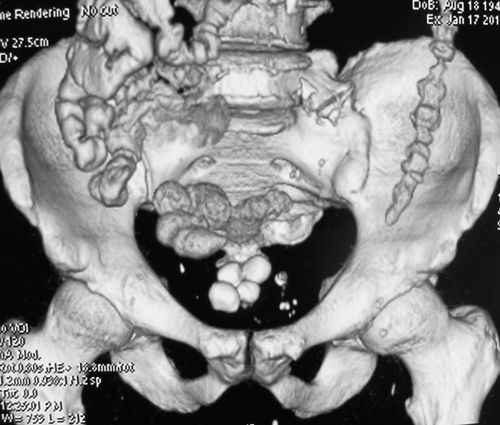

Лучевой цистит с исходом в микроцистис (цистпростатэктомия)